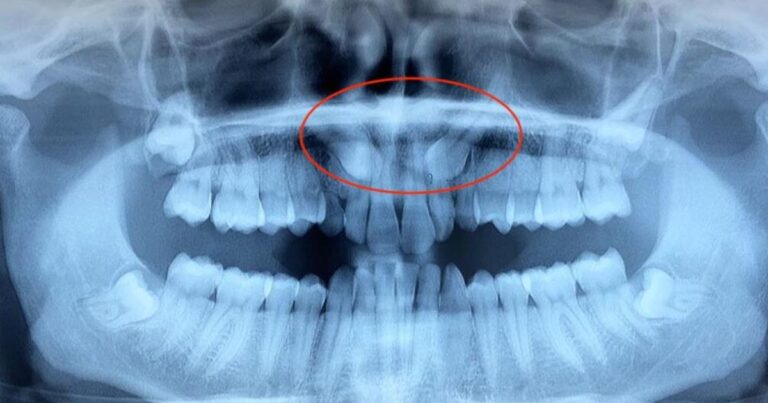

Cosa significa canino incluso Un canino si definisce incluso quando rimane intrappolato nell’osso senza riuscire a erompere nella posizione corretta…